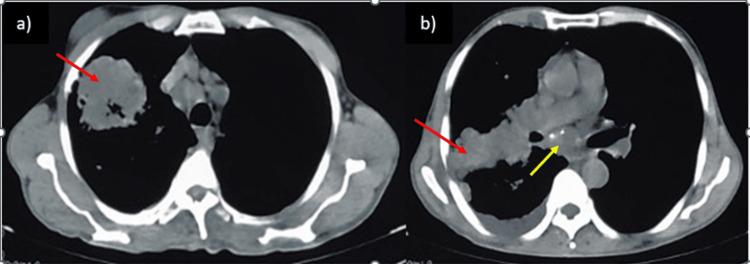

Lung cancer is the most common neoplastic disorder associated with paraneoplastic syndromes. The most common paraneoplastic syndromes are the syndrome of inappropriate release of antidiuretic hormone (SIADH), hypercalcemia of malignancy, ectopic Cushing's syndrome, and various other neurological syndromes. A few case reports have reported gynecomastia as a paraneoplastic syndrome. Recognition of this uncommon presentation can aid in the early detection of associated malignancies, thus potentially improving outcomes. In this article, we are presenting the case of a male patient in his late sixties who, on presentation, had gynecomastia and was eventually diagnosed with non-small-cell lung cancer (NSCLC).

肺癌是与副肿瘤综合征相关的最常见的肿瘤性疾病。最常见的副肿瘤综合征是抗利尿激素分泌不当综合征(SIADH)、恶性肿瘤高钙血症、异位库欣综合征以及各种其他神经综合征。有少数病例报告将男性乳房发育作为一种副肿瘤综合征。认识到这种不常见的表现有助于早期发现相关恶性肿瘤,从而有可能改善预后。在本文中,我们报告了一例60多岁晚期男性患者的病例,该患者就诊时患有男性乳房发育,最终被诊断为非小细胞肺癌(NSCLC)。